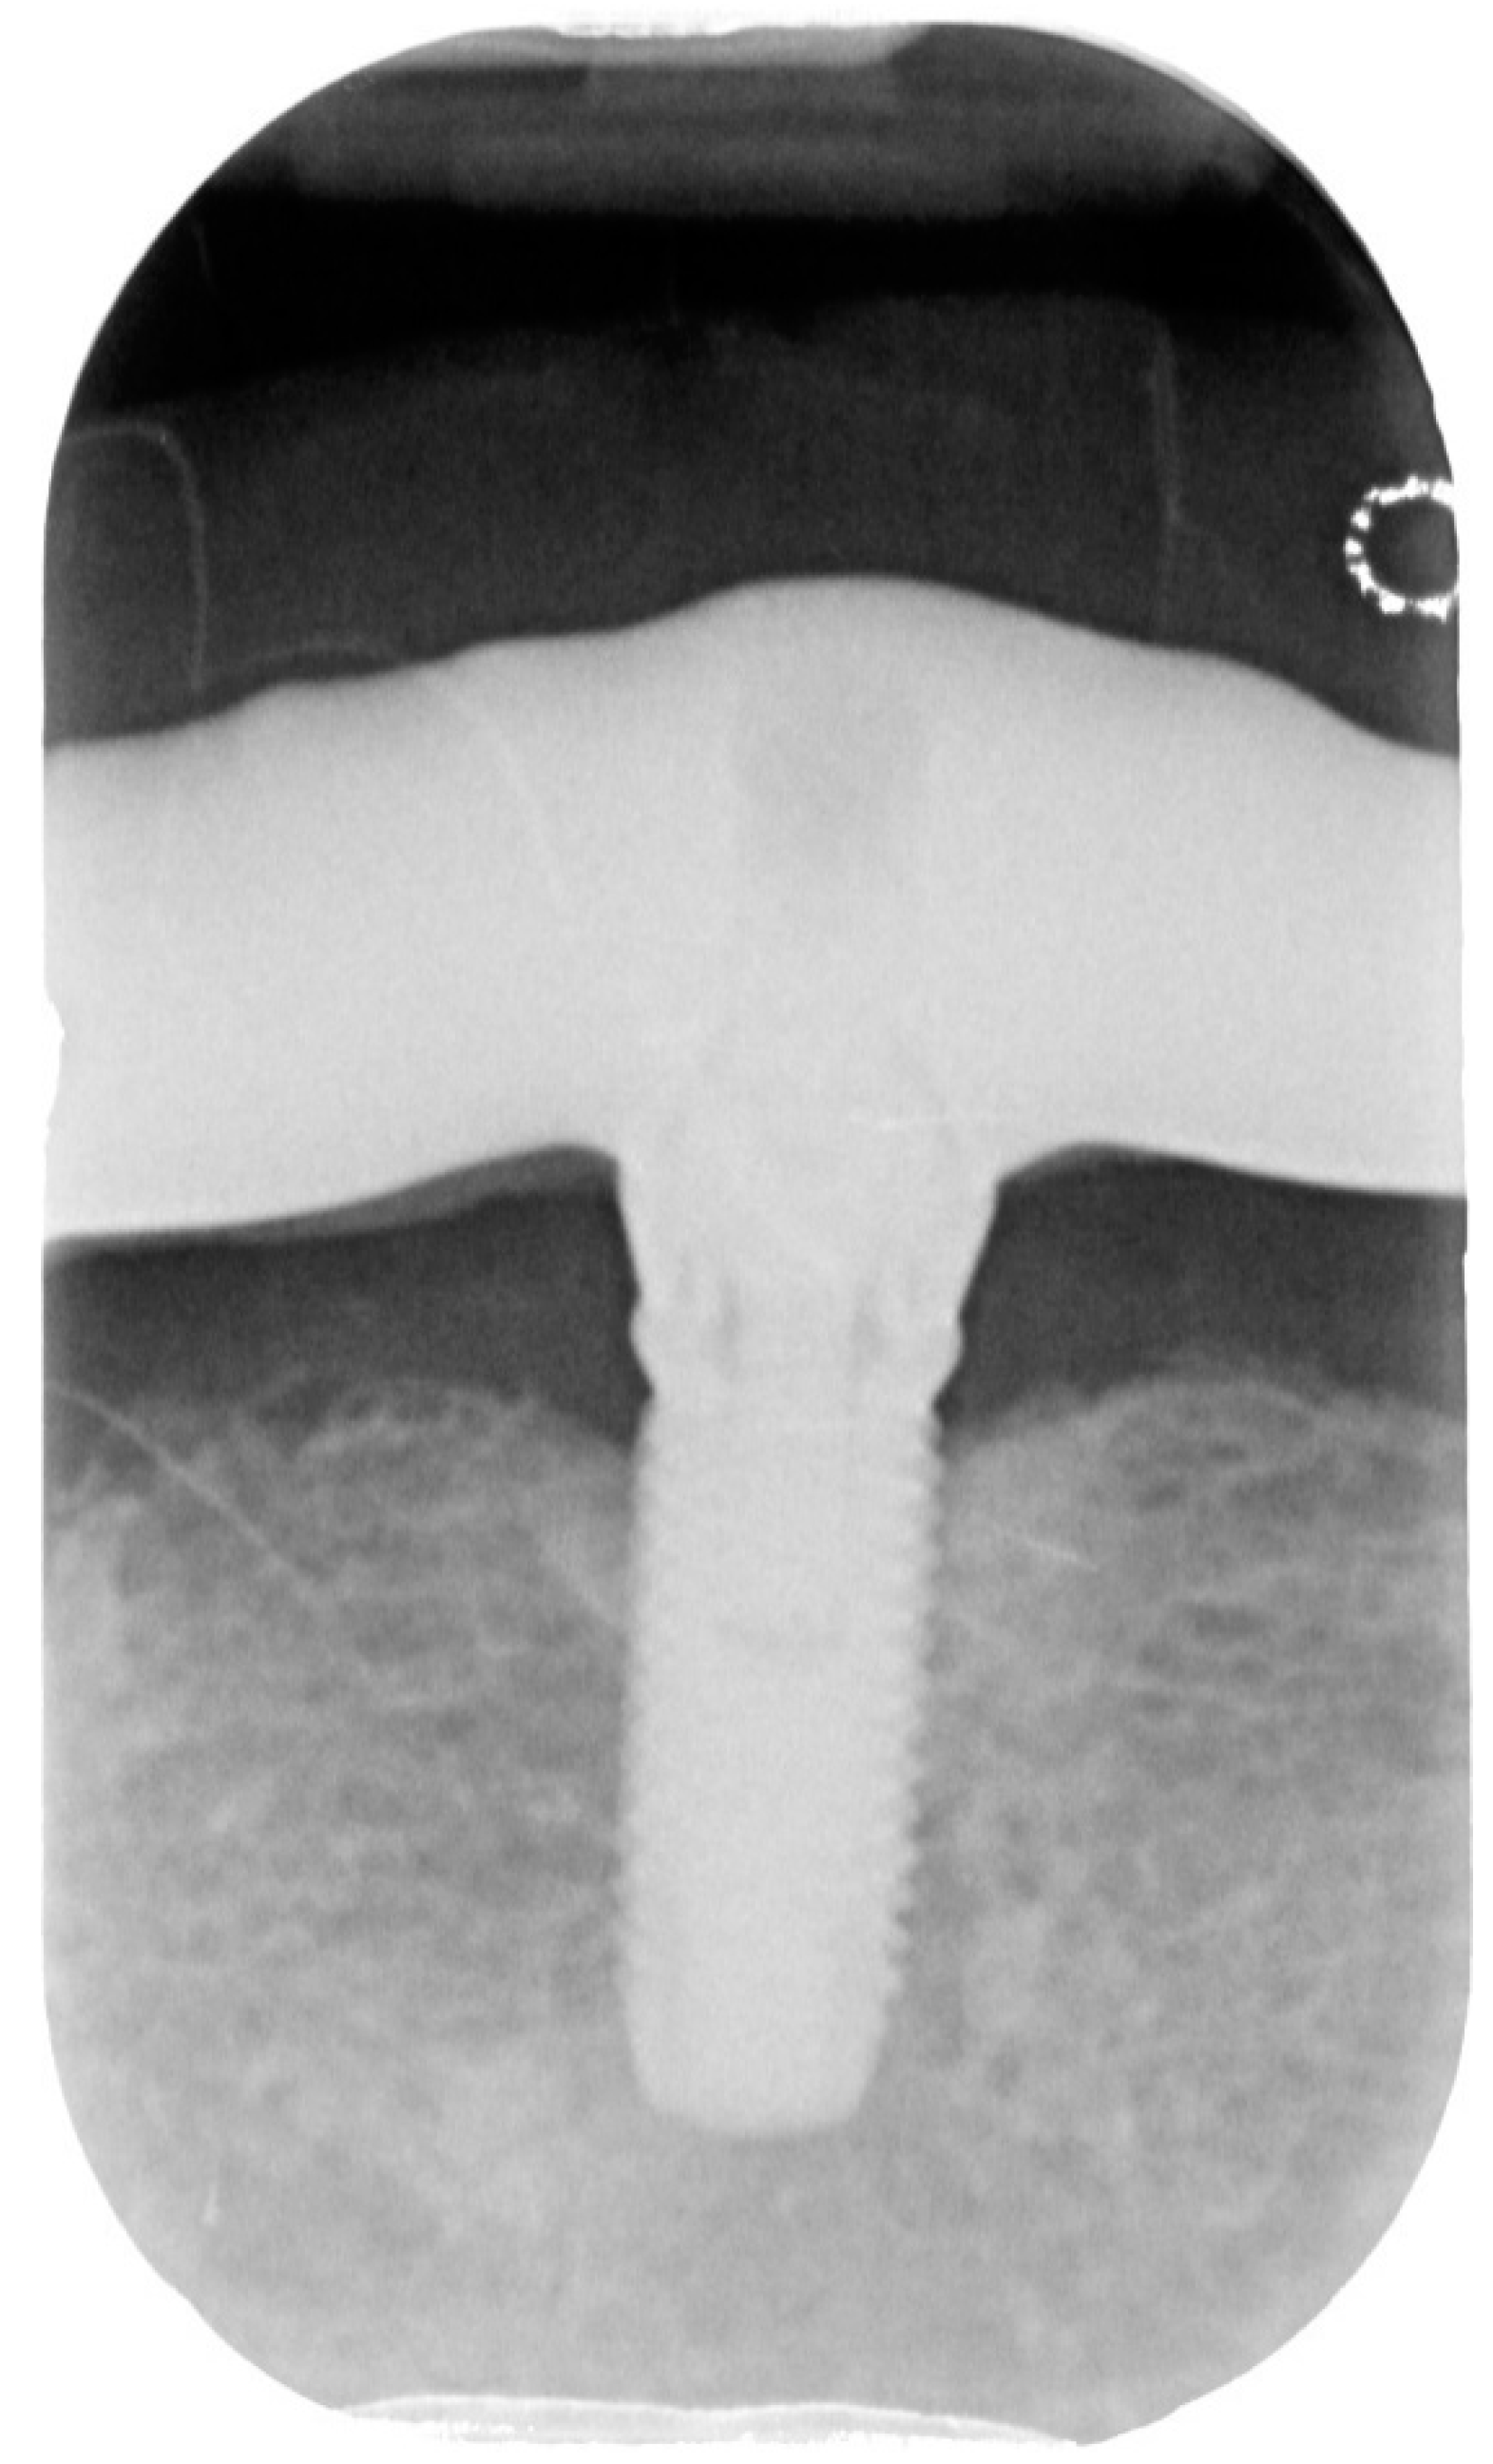

Bidimensional radiographic assessment of the lower jaw implants (with periapical and panoramic radiograph) was done. In the lower jaw, a concave bone resorption of about 2.5 mm mesial and distal to both distal implants were observed, and there was no bone resorption in two central implants (Figure 13 and Figure 14).

Figure 13.

X-ray of 3.5 dental implant in patient in 6 months after treatment.

Figure 14.

X-ray of 4.5 dental implant in patient in 6 months after treatment.